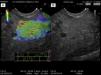

Caso 1Varón de 75 años, con una lesión hipodensa en cuello de páncreas. Se realizó BAAF guiada por USE. El reporte citopatológico fue adenocarcinoma de páncreas. Durante la elastografía, la lesión pancreática presentó una tonalidad azul indicativa de tejido poco elástico y duro, comparado con el tejido periférico observado en color verde, correspondiente al tejido suave (fig. 1).

A) Imagen de elastografía de adenocarcinoma en cuello de páncreas. Se observa un centro en color azul que corresponde al tumor (tejido rígido), sitio donde se realizó la BAAF. Rodeando al tumor, tejido pancreático normal (suave). B) Imagen en modo B de USE de una lesión hipoecoica, heterogénea de bordes irregulares en cuello de páncreas que corresponde a un adenocarcinoma de páncreas en cuello de páncreas. No es posible diferenciar el tumor del tejido pancreático normal circundante.